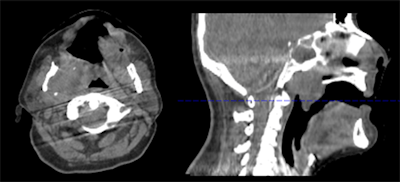

CT is a very fast imaging modality -- with scan times in the order of seconds -- with a very high temporal resolution (about 140 msec for single-source CT and about 70 msec for dual-source CT). Nonetheless, patient motion may lead to motion artifacts, which may result in simple motion blurring, or so-called curved or trochoid artifacts, in case details move at very high speed, such as in the heart (figure 1A).

These artifacts are prominent in cases when patient preparation was not done correctly, when the heart rate is highly variable, or when the gating window does not fall into the best phase. In these cases, new mathematical methods are available that estimate the motion of each voxel and account for that motion (velocity and direction) during image reconstruction. These motion-compensation (MoCo) algorithms have the potential to increase the temporal resolution by about one order of magnitude (figure 1B).